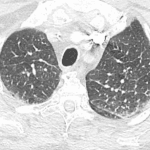

- Mild interstitial pulmonary edema with faint groundglass opacification in the left lung base

- Mild interstitial pulmonary edema

Cardiomegaly with mild interstitial pulmonary edema and likely early alveolar edema in the left lung base.